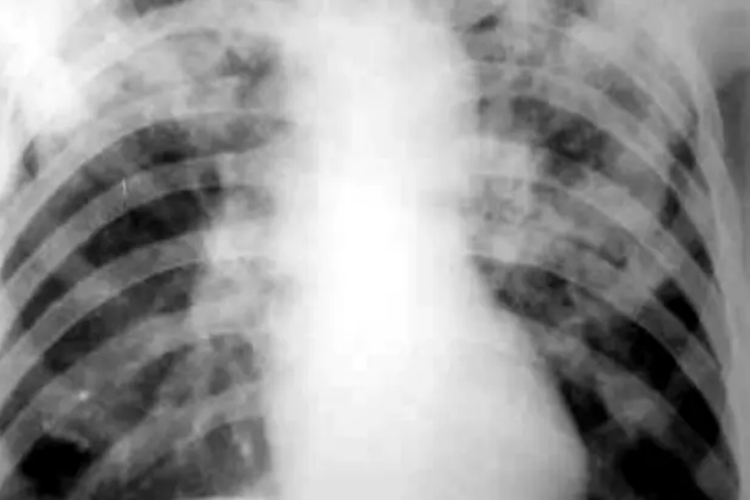

浸润型肺结核表现为肺尖或锁骨上下区大小不等的片状或云絮状密度增高阴影,中心密度较高而边缘模糊。范围较大时可呈肺段或肺叶浸润,往往有渗出、增殖、空洞等病灶并存。

慢性纤维空洞性肺结核一侧或两侧肺上野呈大片致密影,密度不均,其中有单个或多个大小不等的厚壁空洞、广泛的纤维索条影。